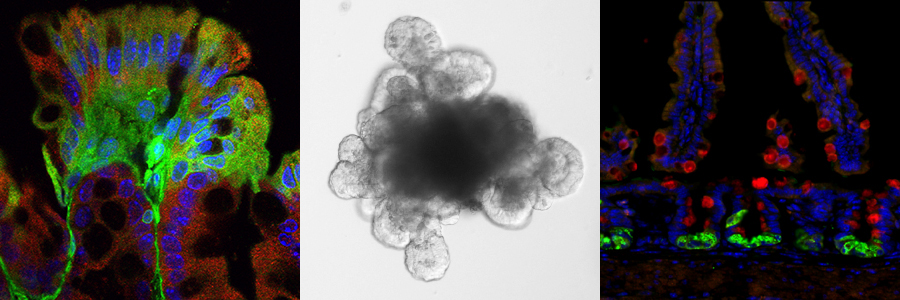

Collage of 3 research images from Wong Lab.

Our stem cell group focuses on understanding the molecular mechanisms underlying regulation of active cycling and quiescent stem cells in the context of intestinal development, tissue regeneration and disease. While stem cell biology is at the forefront of regenerative medicine, there lacks a clear understanding of the general mechanisms that coordinately regulate the various stem cell populations to proliferative and ultimately lineage differentiate in tissue. This lack in knowledge hampers potential to harness stem cell biology for therapeutic purposes in regeneration and disease contexts.

The individual research projects in my laboratory encompass investigation of establishment of the regulatory stem cell niche during intestinal development and the dynamic remodeling of the intestinal stem cell niche during injury and disease.